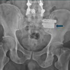

Osteoporosis-related fractures represent a growing global health burden, requiring comprehensive strategies that span risk assessment, prevention, pharmacologic therapy, and surgical care.